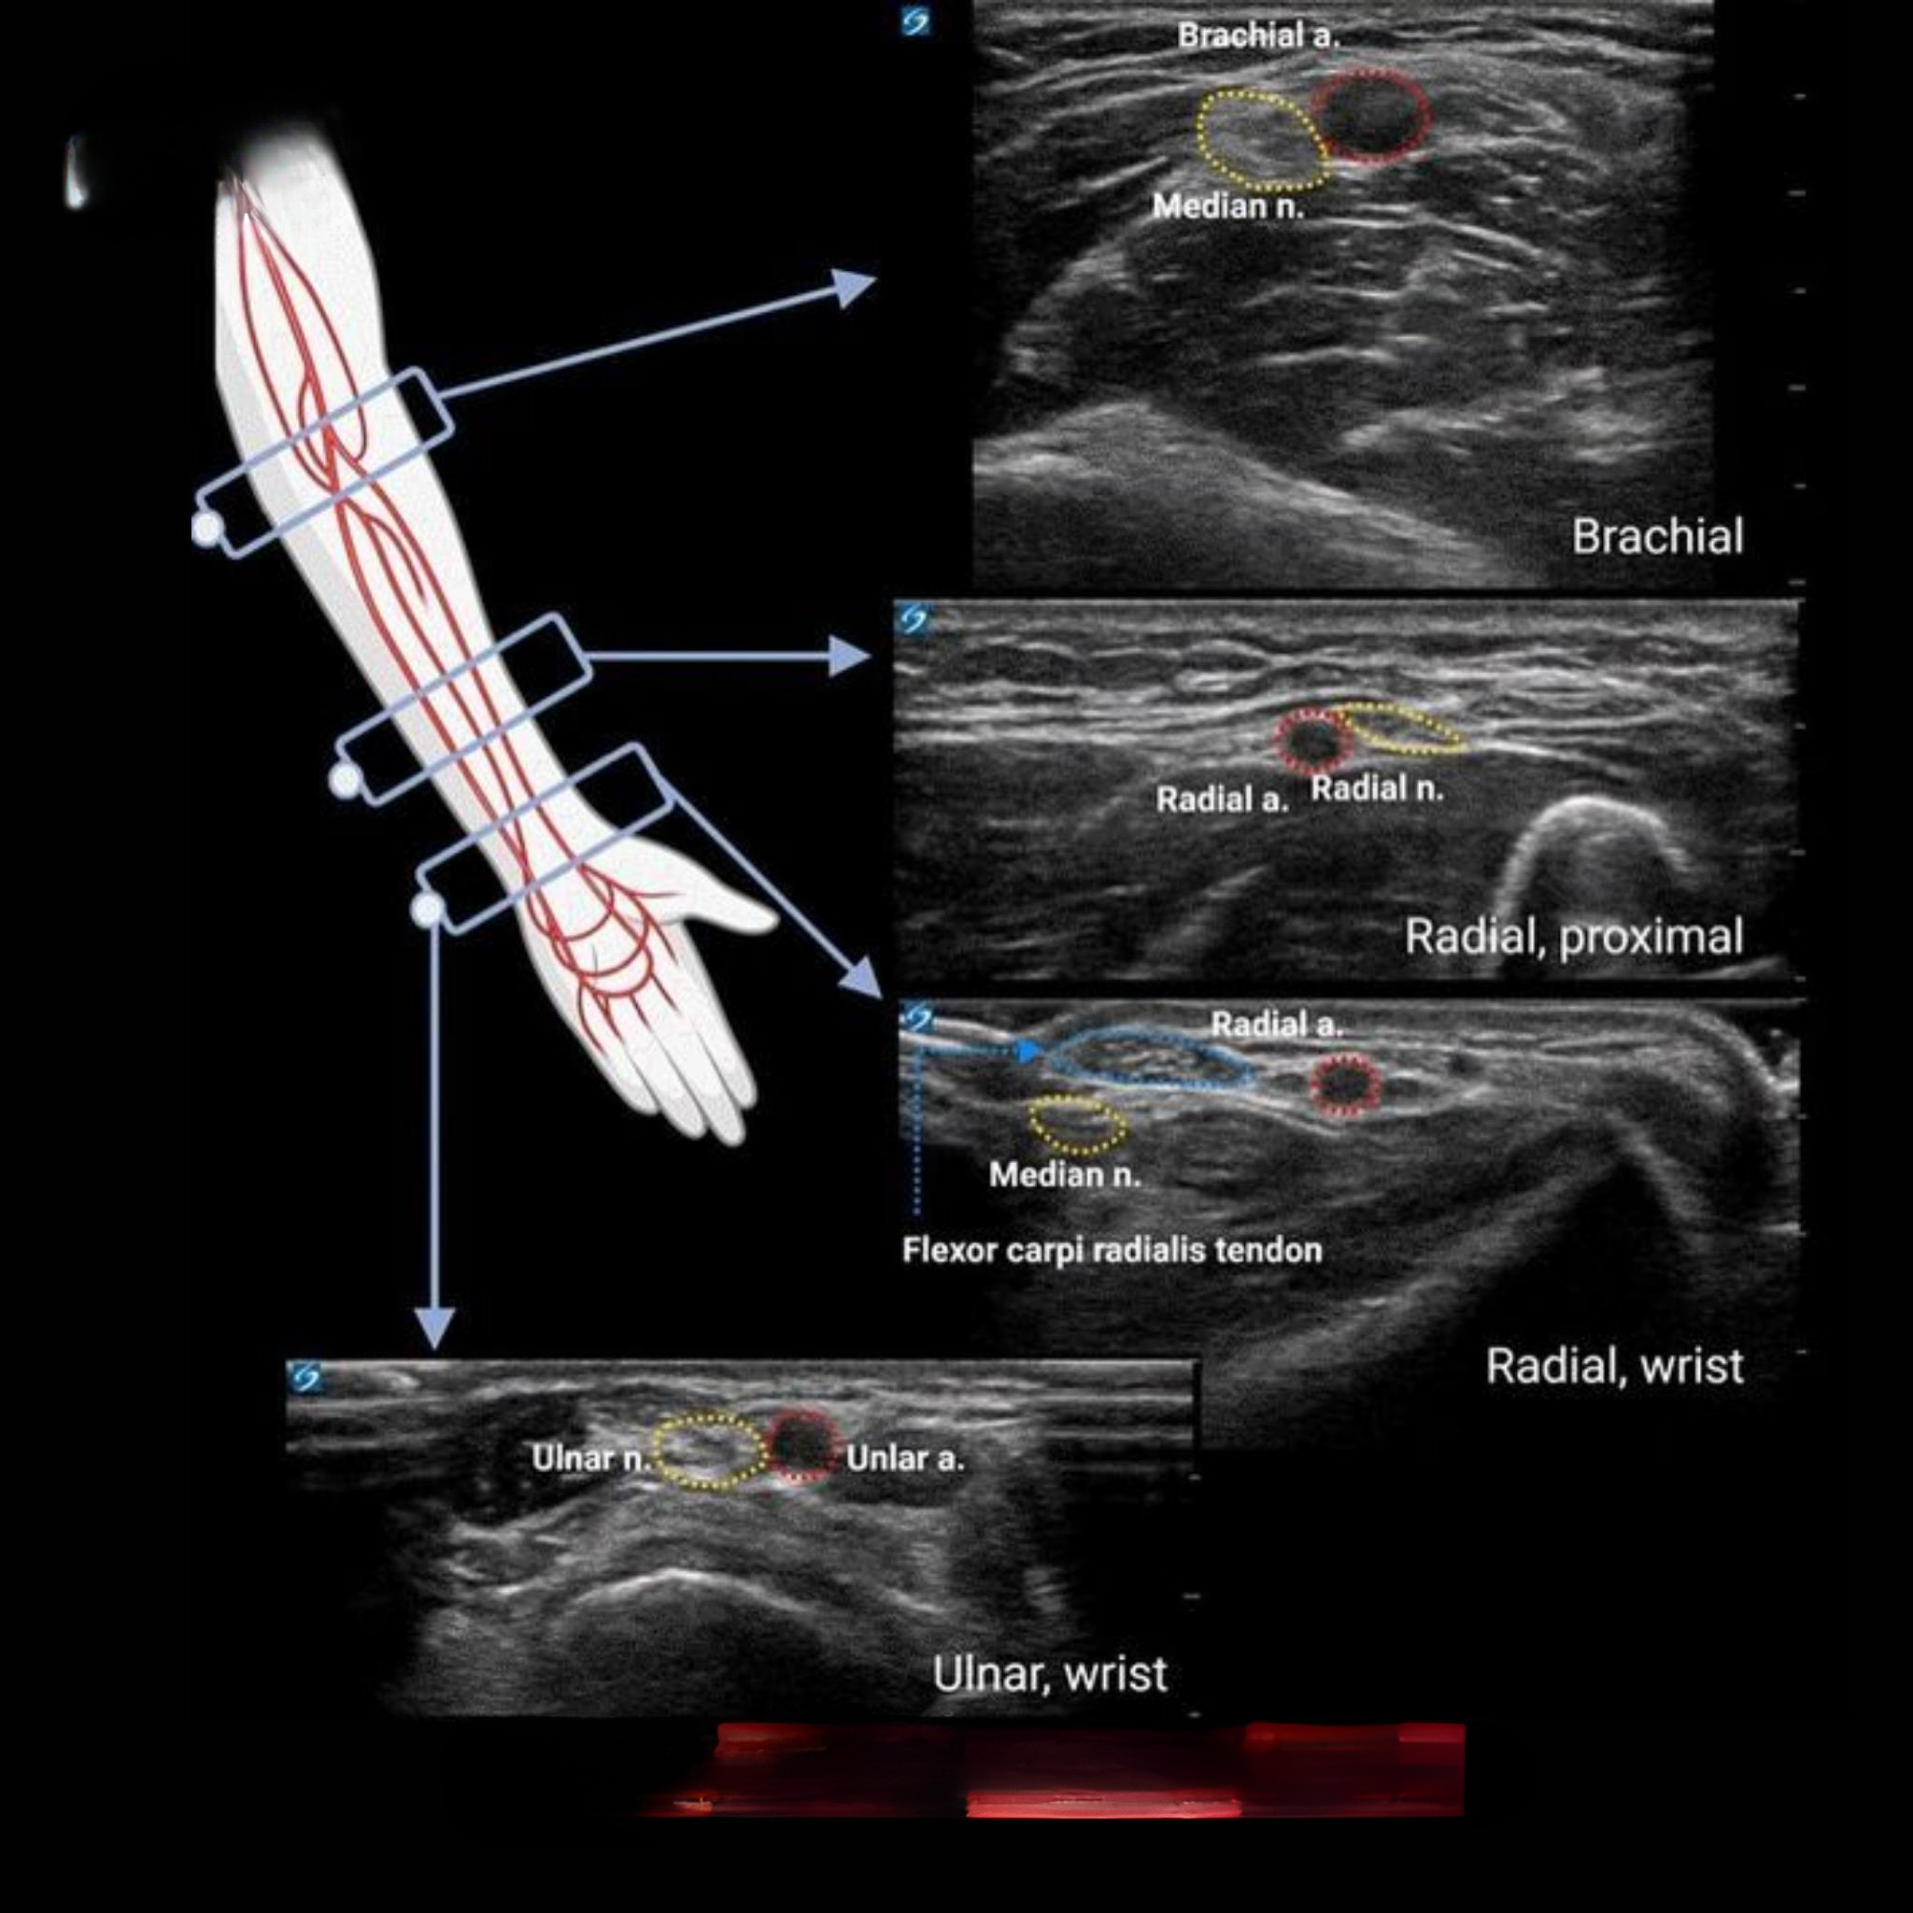

Giải phẫu siêu âm mạch máu chi trên tập trung vào việc hình ảnh hóa các động mạch và dây thần kinh lớn theo trục dọc từ trên xuống dưới. Hình ảnh minh họa thường chia cẳng tay thành các vùng chính: Brachial (cánh tay trên), Radial proximal (đầu gần xương quay), Radial wrist (cổ tay phía quay), và Ulnar wrist (cổ tay phía trụ). Mỗi lát cắt siêu âm trong giải phẫu siêu âm mạch máu sẽ khoanh vùng động mạch bằng màu đỏ – thường tròn, thành dày và đập theo nhịp tim – trong khi dây thần kinh được khoanh màu vàng với cấu trúc "tổ ong" không đập. Sự khác biệt này giúp phân biệt rõ ràng giữa mạch máu và thần kinh, hỗ trợ các bác sĩ trong chẩn đoán và can thiệp.

Trong giải phẫu siêu âm mạch máu tại vùng cánh tay trên, Brachial artery là động mạch chính nuôi dưỡng chi trên, nằm ở vị trí trung tâm. Siêu âm ngang sẽ hiển thị động mạch này như một cấu trúc tròn, hypoechoic với thành dày, dễ dàng theo dõi nhịp đập. Song song với động mạch là Median nerve – dây thần kinh giữa – có hình ảnh hyperechoic với cấu trúc tổ ong đặc trưng. Vị trí này quan trọng trong gây tê vùng cánh tay, nơi giải phẫu siêu âm mạch máu giúp hướng dẫn kim tiêm tránh chạm vào động mạch, giảm nguy cơ tụ máu.

Chuyển xuống vùng đầu gần xương quay, giải phẫu siêu âm mạch máu tập trung vào Radial artery – động mạch quay dễ sờ và thường dùng để đo huyết áp động mạch liên tục (A-line). Trên hình ảnh siêu âm, động mạch này xuất hiện rõ nét với thành dày và dòng chảy pulsatile. Radial nerve nằm gần đó, nhưng ít được nhắm đến trong thủ thuật; tuy nhiên, trong đánh giá tổn thương, giải phẫu siêu âm mạch máu giúp phát hiện bất thường như huyết khối hoặc chèn ép.

Tại cổ tay phía quay, giải phẫu siêu âm mạch máu dễ tiếp cận cho gây tê Median nerve và xác định Radial artery khi thực hiện A-line. Flexor carpi radialis tendon đóng vai trò mốc giải phẫu quan trọng để định vị dây thần kinh giữa, hiển thị như cấu trúc hyperechoic tuyến tính trên siêu âm. Động mạch quay ở đây nông, dễ hình ảnh hóa, giúp bác sĩ tránh đâm kim vào mạch máu trong thủ thuật.

Ở cổ tay phía trụ, Ulnar artery và Ulnar nerve chạy gần nhau, nằm trong gân gấp cổ tay trụ. Giải phẫu siêu âm mạch máu hiển thị động mạch ulnar với dòng chảy rõ ràng, trong khi thần kinh ulnar có cấu trúc tổ ong bên cạnh. Vị trí này quan trọng cho gây tê vùng cổ tay và kiểm tra hội chứng ống Guyon – một tình trạng chèn ép thần kinh gây tê bì.